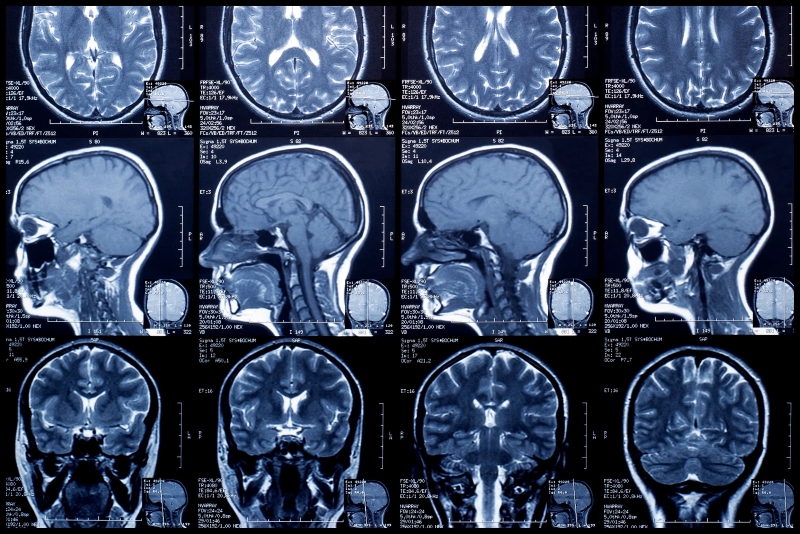

MRI là viết tắt của Magnetic Resonance Imaging, nghĩa là Chụp cộng hưởng từ. Đây là phương pháp chẩn đoán hình ảnh không xâm lấn đặc biệt quan trọng trong y học hiện đại, giúp tạo ra hình ảnh chi tiết của các cấu trúc bên trong cơ thể mà không dùng đến bức xạ ion hóa như tia X.

Chụp MRI hiện không chỉ là một kỹ thuật chụp hình mà còn là một quy trình y khoa được chuẩn hóa nghiêm ngặt. Nó có khả năng cung cấp hình ảnh với độ phân giải cao cùng độ tương phản mô mềm vượt trội.

Khi được ứng dụng đúng cách, chụp MRI là giải pháp lý tưởng để chẩn đoán, quản lý và điều trị các bệnh lý cần đánh giá mô mềm chi tiết. Chẳng hạn như chẩn đoán các bệnh lý thần kinh (u não, nhồi máu não, tủy sống), bệnh lý cơ xương khớp (thoát vị đĩa đệm, rách dây chằng), hoặc đánh giá các khối u mô mềm.